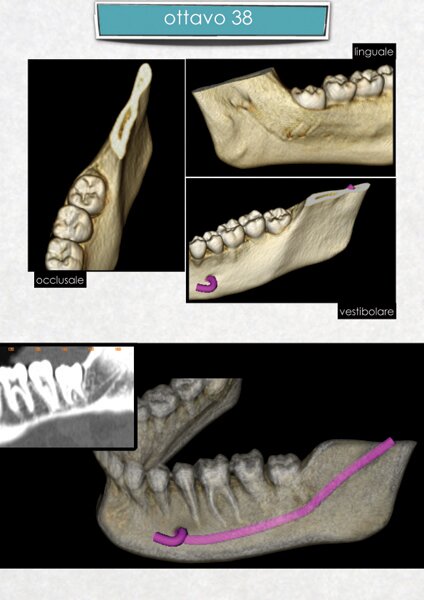

La diagnostica dei casi complessi di chirurgia orale ed implantologia è realizzata, a partire da una TAC dentale a cui si sottopone il paziente, mediante l'utilizzo del software computerizzato ONE SCAN 3D. Attraverso questo programma è possibile ottenere una ricostruzione tridimensionale del mascellare/mandibola del paziente, identificare le strutture anatomiche di riferimento, valutare i tessuti duri e molli, pianificare l'inserimento degli impianti nell'osso disponibile e ottenere un valido consenso informato del paziente all'intervento chirurgico.

Questo approccio moderno e tecnologico consente all'odontoiatra di lavorare con la massima serenità,riducendo al minimo qualsiasi imprevisto in fase operatoria.